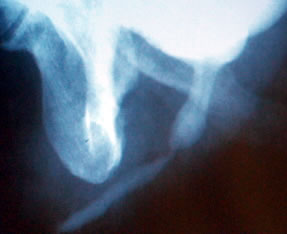

Проксимальные

бульбарные стриктуры уретры